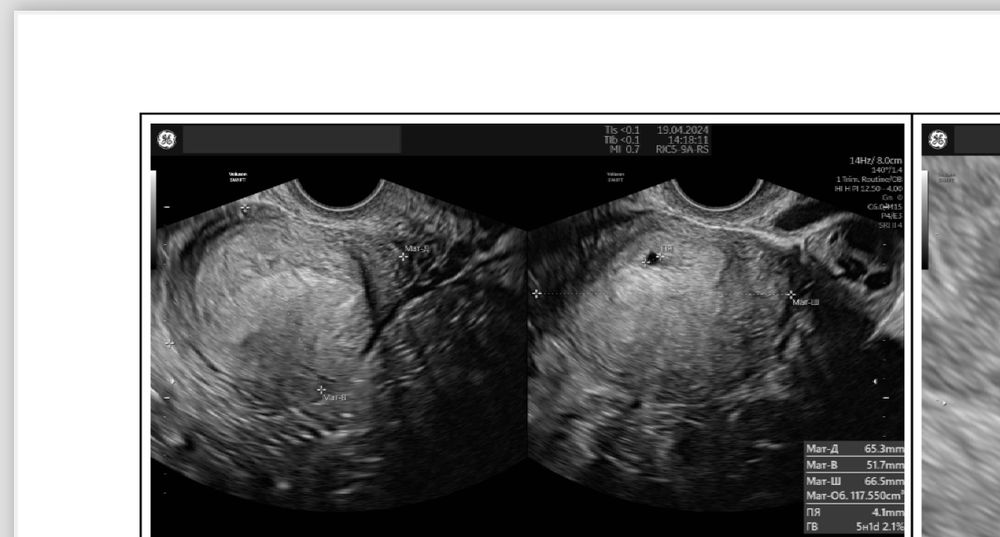

Я конечно до сих пор не могу понять как так получилось…Неделю назад нашли плодное яйцо в матке ,где уже был и желточный мешок и ктр…Вчера утром начались резкие боли до потери сознания..Сразу же на скорой отправили в больницу ,сделали узи и экстренно прооперировали..Лопнула труба,началось внутреннее кровотечение ,на момент операции давление было 70/40, и я потеряла более двух литров крови ..Сейчас в реанимации ((Ну как так ,а как же прошлое узи (((

Мама ангелочка и дочек, кровотечения из матки не было . Я спрашивала после операции, мне матку не чистили .Перед операцией когда делали узи,там вся брюшная полость была в крови ,ничего не было видно